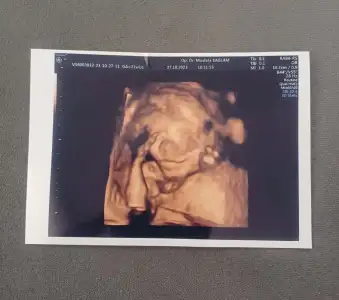

Oğluşumdan herkese hayırlı cumalar teyzeleri 😍🤲

• 20231027_112621.webp

20231027_112621.webp

66,5 KB · Görüntüleme: 87